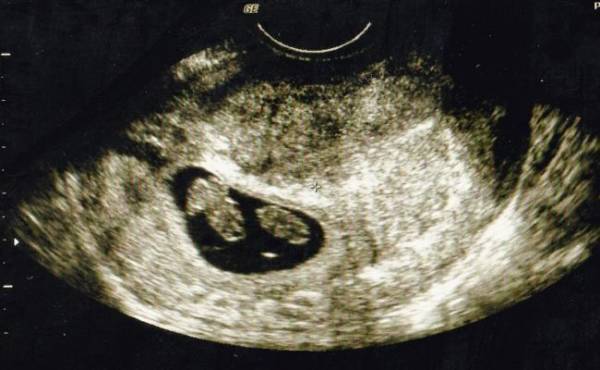

エコーで確認すると3人分の心拍が!

私が3人目を妊娠したのは長男が3歳、次男が1歳のときでした。そろそろ赤ちゃんの心拍が確認できるかな? なんて期待を胸に抱きながら、内診台でエコーを見ていると見覚えのある袋が2つ? その中には心拍のように動いて見えるのが3つ?

私が混乱していると、先生が「お母さん。赤ちゃん何人か見える?」と聞いてきました。先生と一緒に確認し、見事に3人の心拍を確認! パニックで笑うことしかできず、頭のなかは真っ白で少しの間その場から動けませんでした。